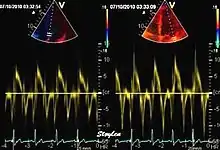

relation between mitral flow and mitral annulus velocity. Left: Normal person with good diastolic function; high E and e', normal E/e'. Middle, patient with diastolic dysfunction without increased filling pressure; low E and e', normal E/e' ratio. Left, patient with diastolic dysfunction and increased filling pressure; high E, low e' and high E/e'. The S' is reduced in proportion to the e'

During the two filling phases, there is early (E) and late (A) blood flow from the atrium to the ventricle, corresponding to the annular velocity phases. The flow, is driven by the pressure difference between atrium and ventricle, this pressure difference is both a function of the pressure drop during early relaxation and the initial atrial pressure. In light diastolic dysfunction, the peak early mitral flow velocity E is reduced in proportion to the e', but if relaxation is so reduced that it causes increase in atrial pressure, E will increase again, while e', being less load dependent, remains low. Thus, the ratio E/e' is related to the atrial pressure, and can show increased filling pressure[15][16] although with several reservations.[17][18] In the right ventricle this is not an important principle, as the right atrial pressure is the same as central venous pressure which can easily be assessed from venous congestion.[19][20]